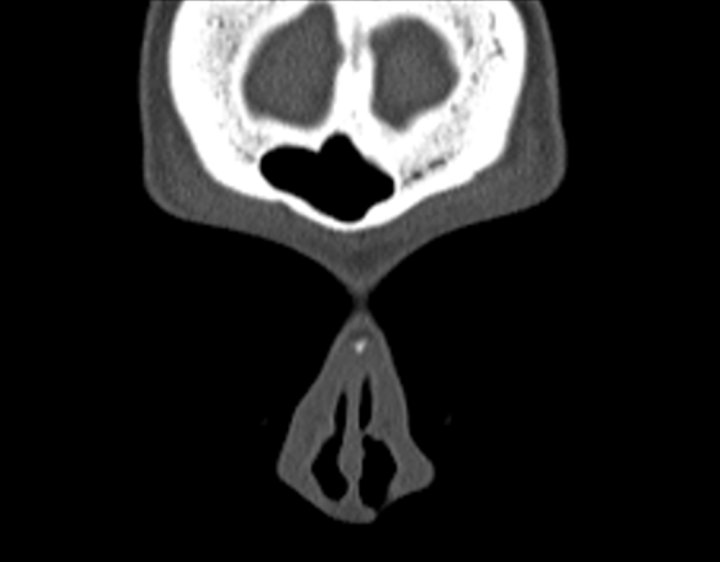

Click any image for labels.